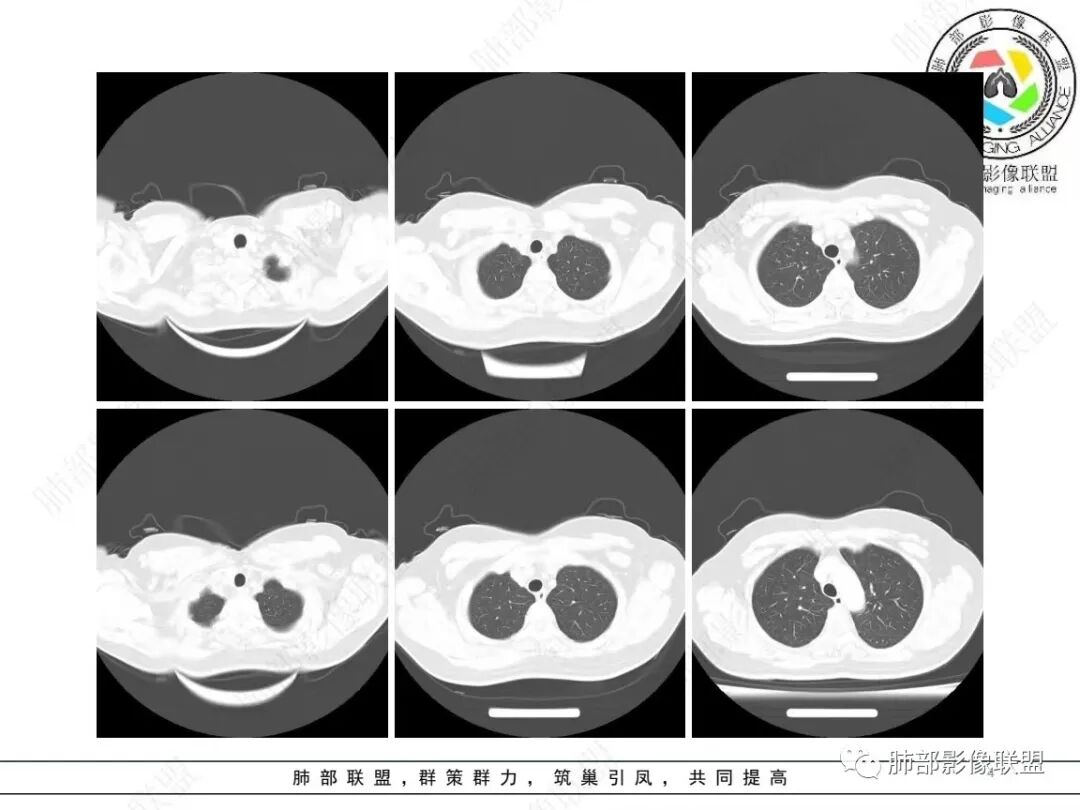

2、影像特点:右肺下叶胸膜下不规则结节,矢状位整体病灶沿着支气管方向呈斑片状,不均匀强化。病灶边缘多平直、凹陷(从部分层面可见极其像月牙铲),缺乏膨隆感,周围可见多发长索条影,病灶内可见多发充气支气管影,大部分支气管完全贯通病灶并轻度扩张,极少支气管进入病灶内堵塞,观察横断位视频、部分层面病灶周围可见边界欠清的ggo。纵隔窗病灶内未见明显钙化影。未见卫星病灶及树芽征。

3、综合分析:中老年女性胸膜下不规则结节,无特殊临床表现,实验室检查亦无特殊,病灶在部分断面呈斑片状,边缘多平直甚至凹陷,缺乏分叶及膨隆感,未见粗短毛刺及胸膜凹陷,部分层面似见”月牙铲“样外形,但缺乏张力的“月牙铲”不太可靠。灶周磨玻璃晕也会让人警惕肺腺癌可能,磨玻璃影边界是否清晰常须薄层仔细分辨。

实性密度为主结节影,支气管密切相关,边缘多平直,缺乏分叶膨隆感,缺乏张力,有磨玻璃晕但边界不清。更符合慢性炎性病变。

病理提示隐球菌感染可能。肺部隐球菌感染孤立性病灶与肺腺癌的鉴别诊断是个永恒的话题。